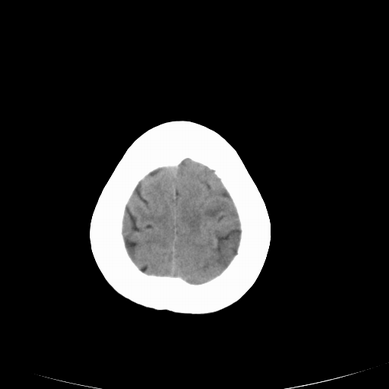

以下是引用jsgdoctor在2008-7-16 23:11:00的发言:[br]左侧大脑中动脉供血区脑梗塞